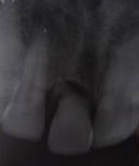

Pre Operation X-ray

Placement of Bone Grafting

Use of Bone Graft & GTR membrane for an Implant